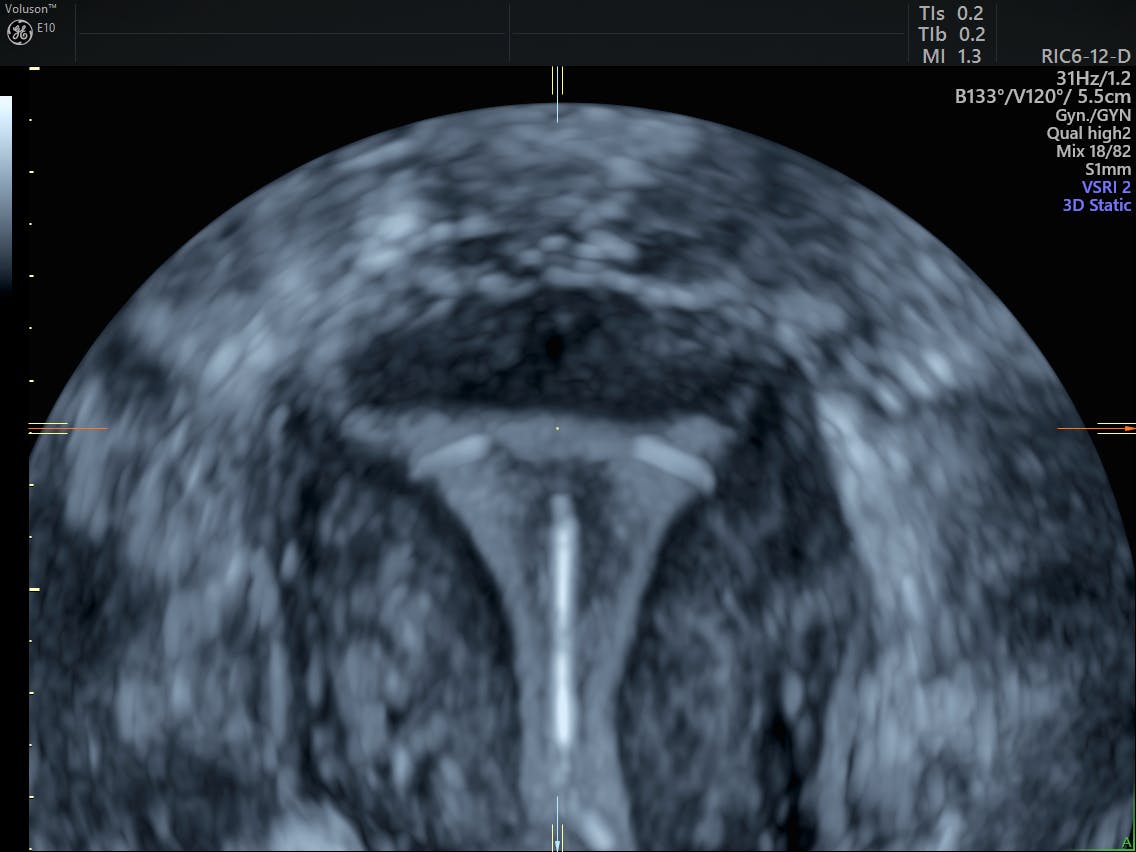

What S The Difference Between 3d And 4d Ultrasound Scans